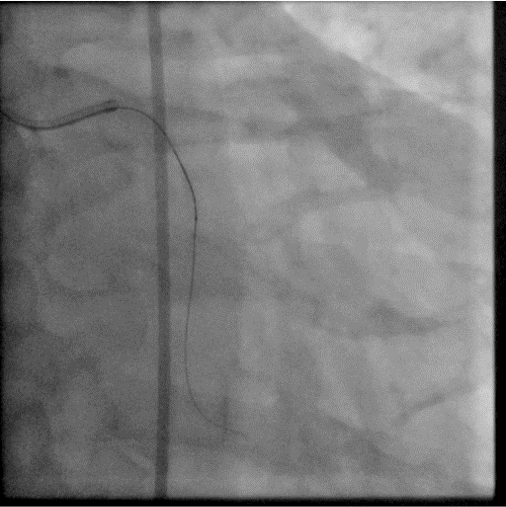

For 2nd stage procedure, we did the RCA CTO with primary retrograde approach due to ambiguous proximal cap and distal cap is a bifurcation. The initial retrograde wire escalation technique was failed to puncture into the distal cap by using SIon, Gladius EX and even Gaia 3rd wire. So we shift to antegrade approach starting with Gladius EX wire but we failed too. Then retrograde puncture was reattempted with Miracle 6 wire. It successfully punctured into the distal cap. By using kissing wire technique, antegrade wire entered distal true lumen. The procedure was finished with balloon dilatation and stenting. We were abled to preserve the distal PL and PDA branch.